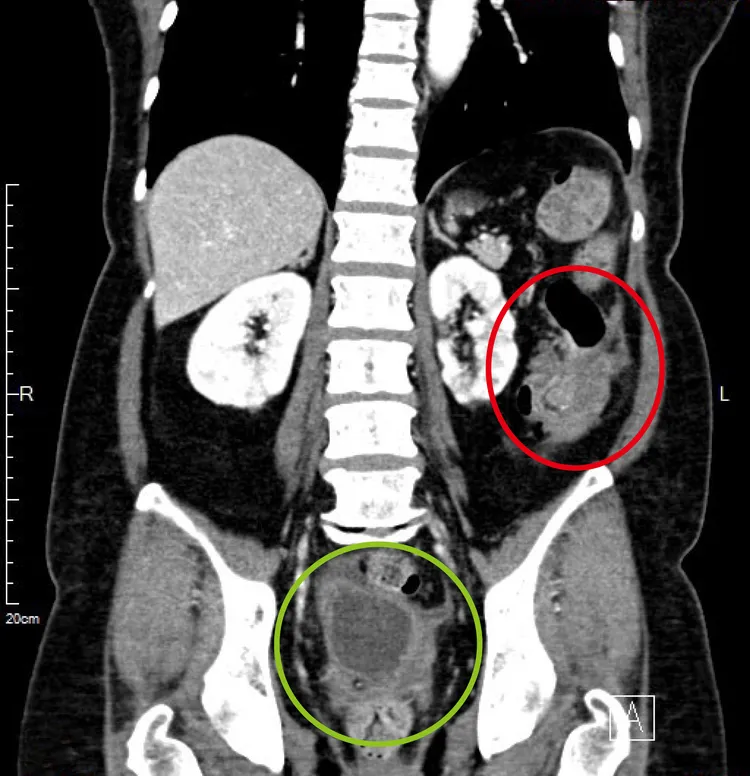

腫瘤造成大腸套疊,紅圈處為大腸癌,綠圈處為骨盆腔腹膜黏液性腫瘤。馬偕提供